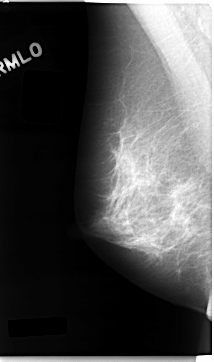

C_0026_1.LEFT_MLO

LEFT_MLO LINES 4656 PIXELS_PER_LINE 2752 BITS_PER_PIXEL 12 RESOLUTION 50 OVERLAY